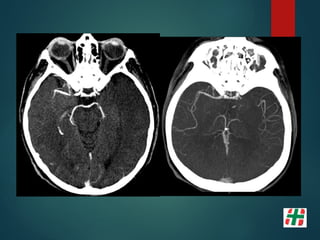

Patología Estenótica

NASCET= (B-A)/B x 100% estenosis

ECST= (C-A)/C x 100 % estenosis

Stroke, 2004; 35: 1 a 6

FORMAS DE CUANTIFICACIÓN

AJ Fox. How to measure carotid stenosis. Radiology 1993; 186: 316.

Paciente mujer 56 años, fumadora.

Episodios repetidos de déficit

transitorios en ambos hemicuerpo,

mayormente del lado derecho.

MOYA MOYA